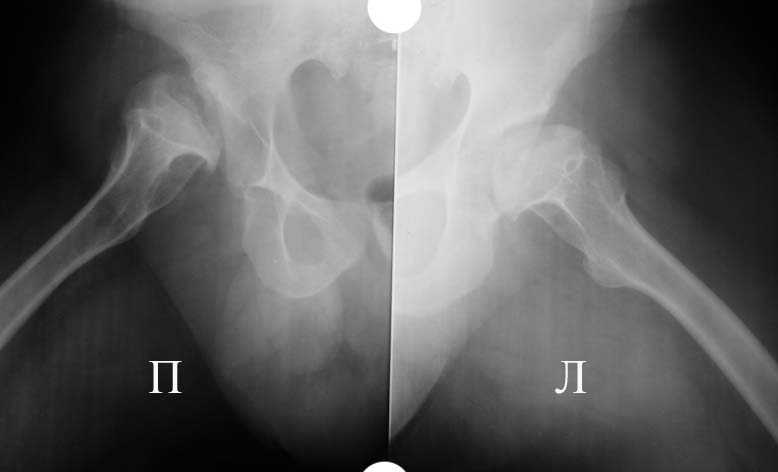

Аксиальная проэкция обоих т/б суставов

Алексей, судя по снимкам, правый тазобедренный сустав нуждается в замене. Думаю, что получится поставить протез без дополнительных конструкций во впадину и особых ножек. Важным является диаметр канала. Надо по шаблонам оценить размер. Самые маленькие из известных мне ножек в России предсталены у De Puy (бесцементная 6), и новинка от BIOMET бесцементная диспластическая ножка.

Алексей, качество Р-грамм не очень хорошее, канал виден только в одной плоскости (по-моему аксиальной), размеры кости не понятны. Думаю что можно подрыться без к/пластики, но головка то есть всегда. Канал не виден, ничего не могу сказать. Но наверно можно Аллоклассик с подстраховкой Вагнером.

Если есть возможность прислать снимки таза и прямую проекцию тазобедренного сустава с бедром, то можно будет обсудить и вероятность и перспективы.